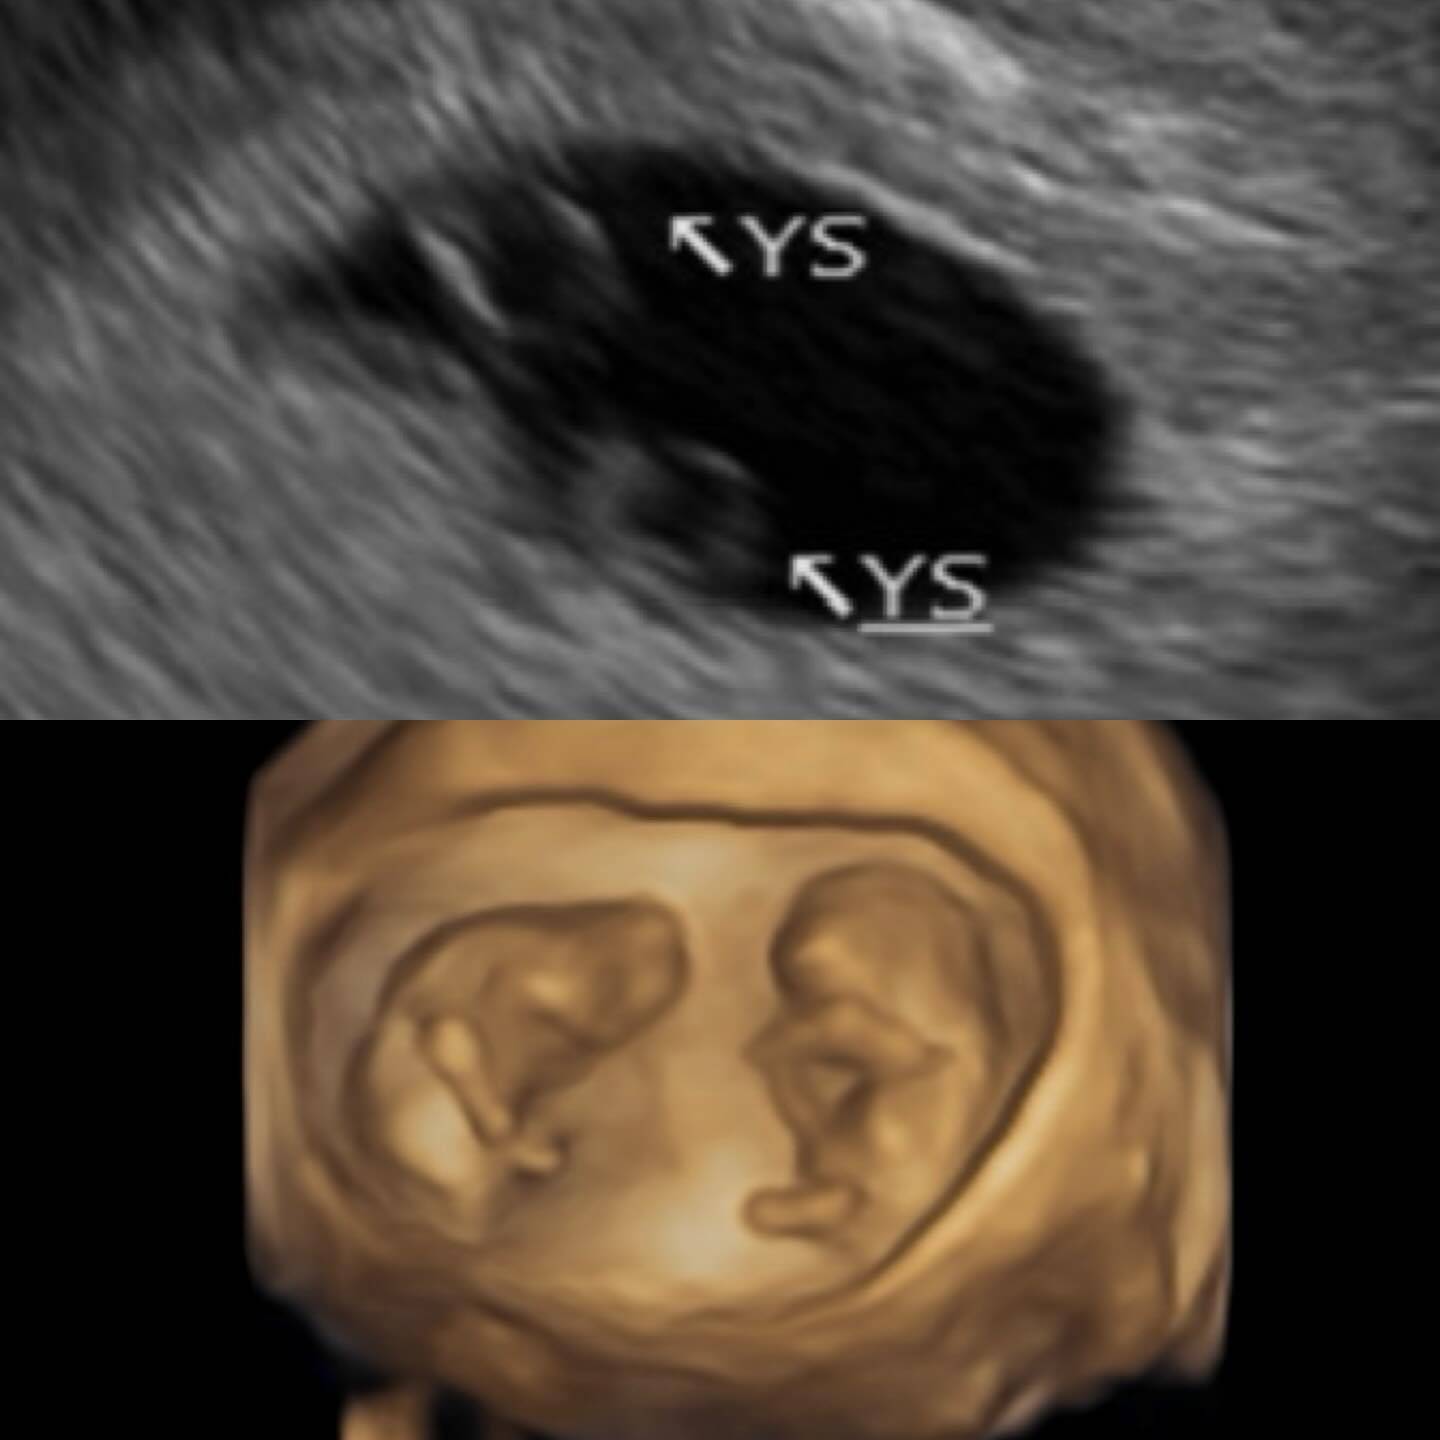

鄭家純在Threads平台上開心宣布:「向大家報告喜事,阿純目前懷孕12週,是同卵雙胞胎。」她分享了清晰的超音波照片,可見兩個小生命在同一個胎囊內健康成長。這個消息一出,立即引來大批粉絲湧入留言祝福,紛紛為這位新手媽媽感到開心。鄭家純透露,這次懷孕完全是意外驚喜,因為她原本乖乖避孕,沒想到小產後的排卵期大幅延後,竟然在月經尚未恢復前就再次自然受孕。

回憶起產檢過程,鄭家純表示最初在東京診所只能確認子宮內著床,直到回台灣茂盛醫院複檢時,超音波師在同一個胎囊中發現兩個卵黃囊,驚喜宣布是雙胞胎。她哽咽分享:「寶寶們很貼心,讓我在6週就聽到心跳,聽到的瞬間眼淚就掉下來,因為上次沒有聽到。」這句話背後隱藏著她上次懷孕時胚胎只發育到5週,在9週時自然小產的痛苦經歷。由於同卵雙胞胎風險較高,她坦言初期十分焦慮,直到8週確認為雙羊膜後才稍稍寬心。